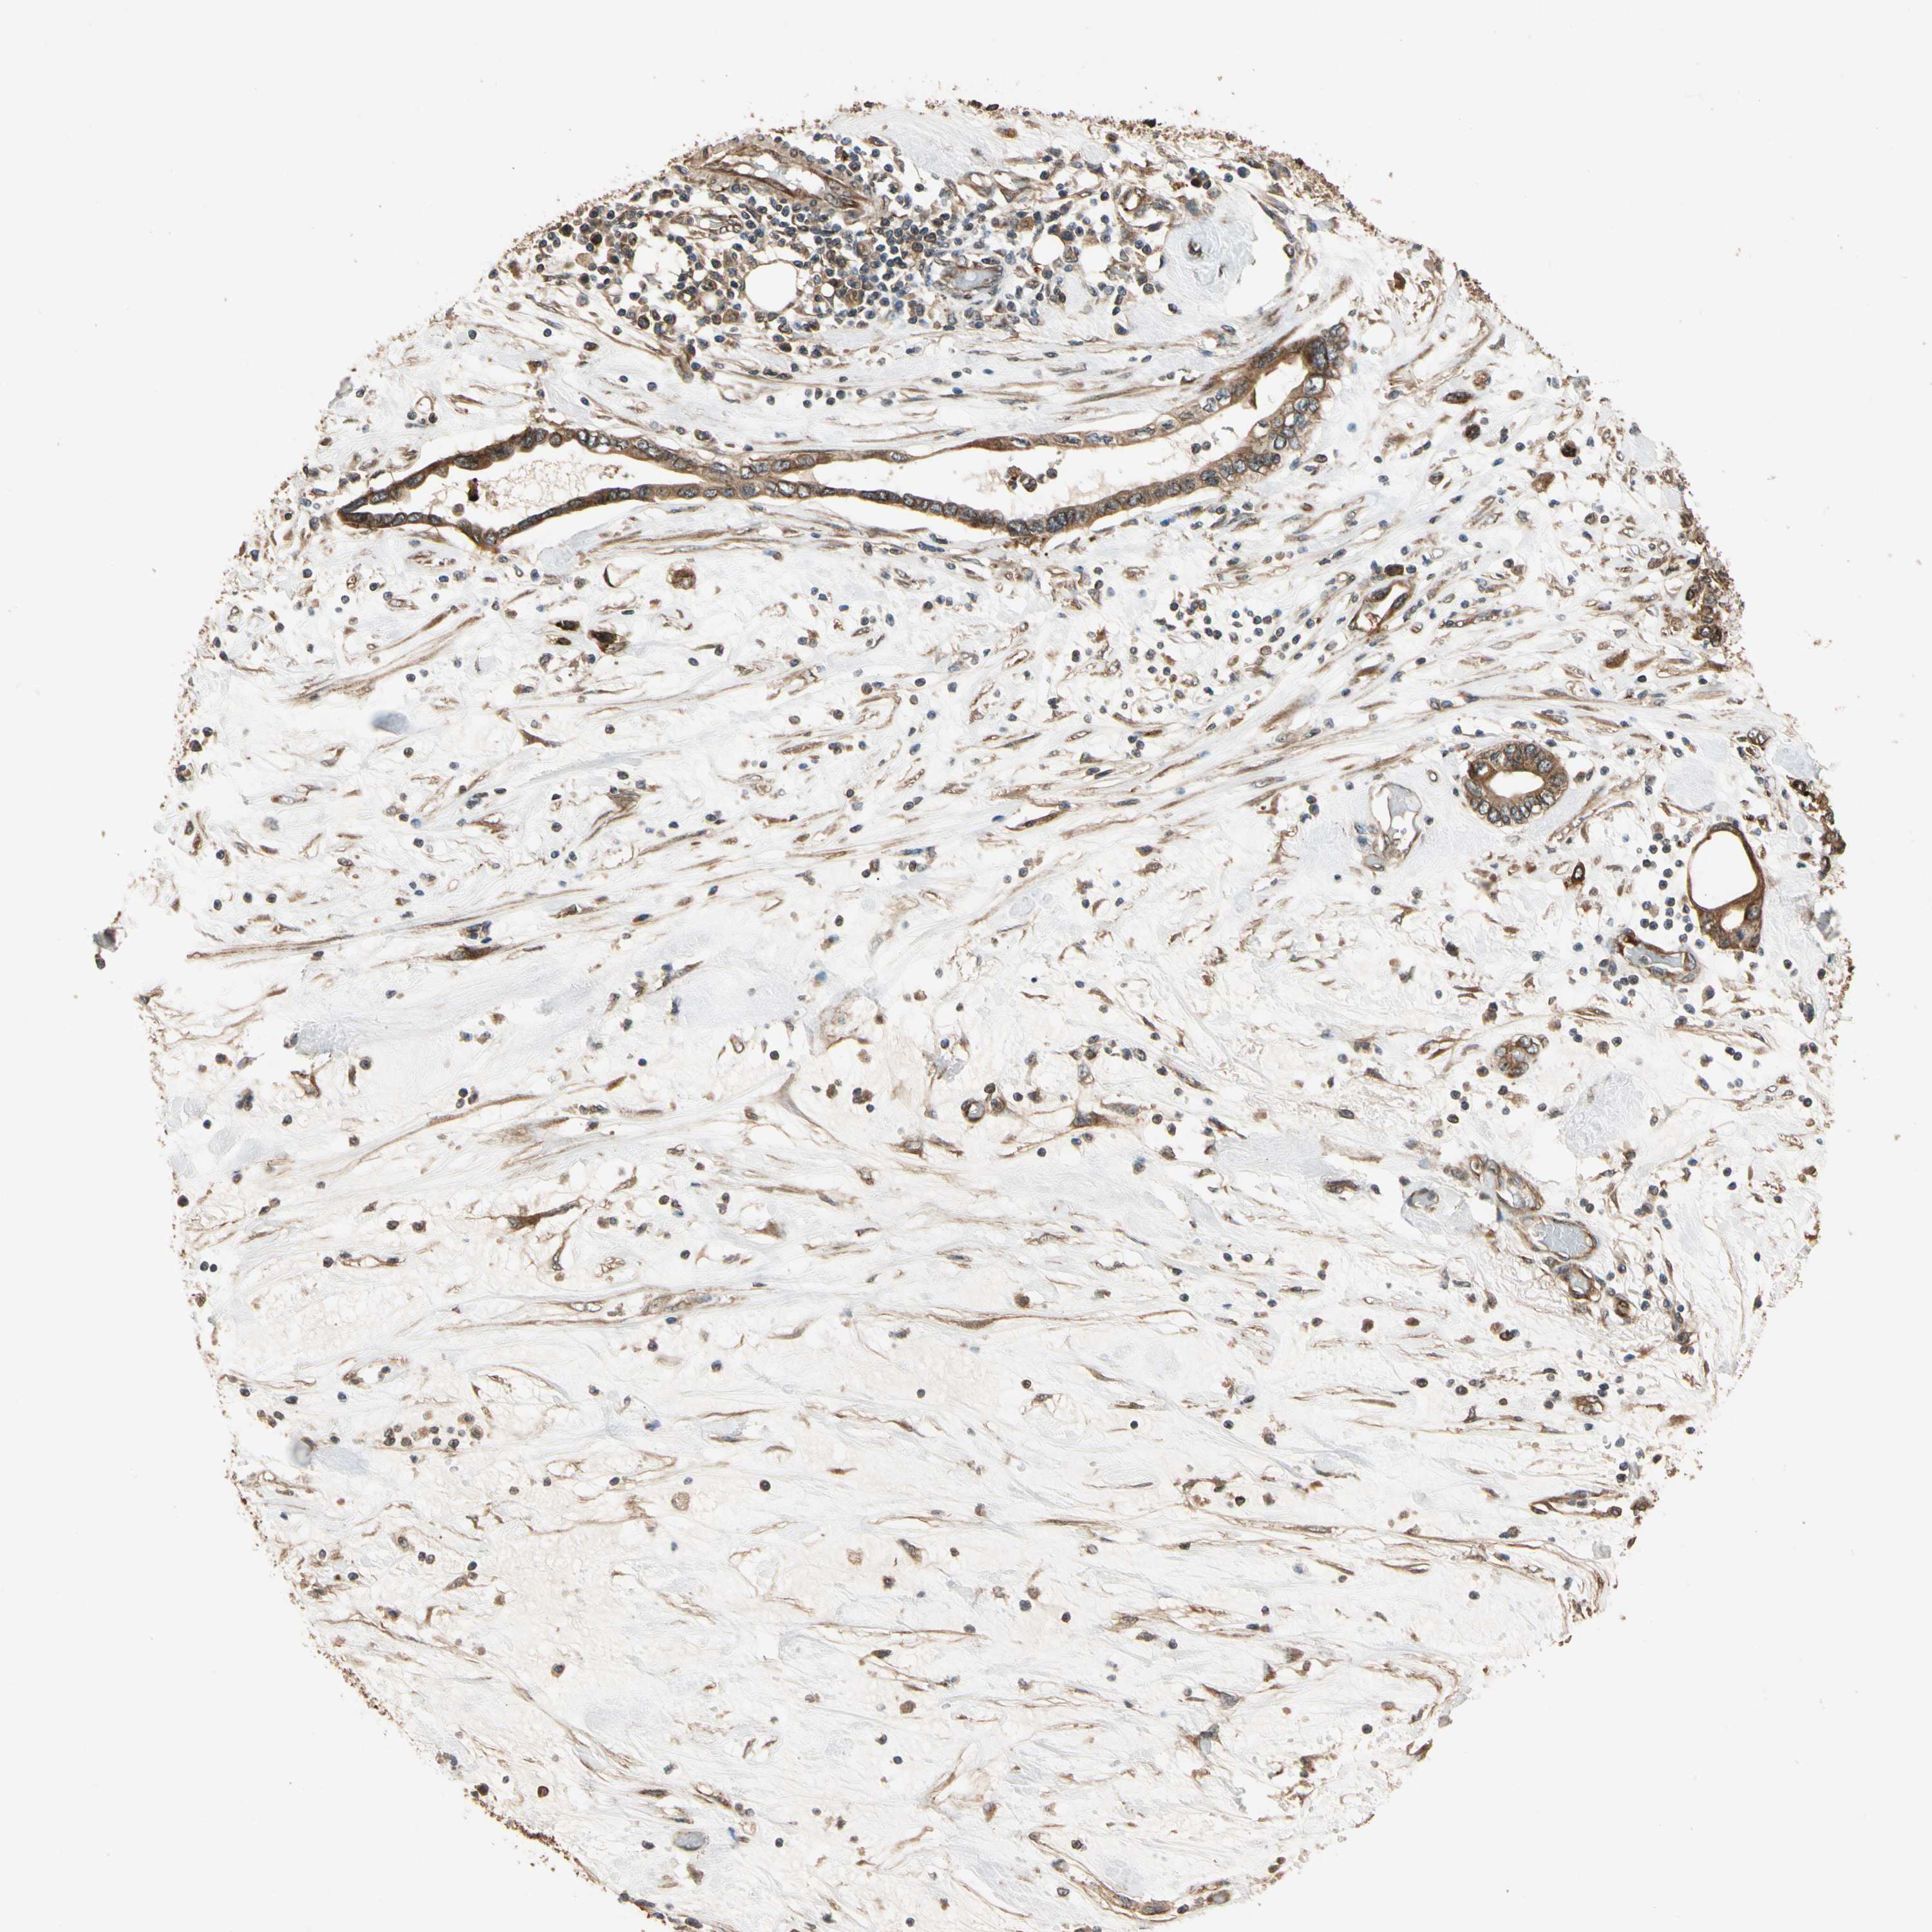

PANCREATIC CANCER - Protein expressioni

A mouse-over function shows sample information and annotation data. Click on an image to view it in a full screen mode. Samples can be filtered based on level of antibody staining by selecting one or several of the following categories: high, medium, low and not detected. The assay and annotation is described here.

Note that samples used for immunohistochemistry by the Human Protein Atlas do not correspond to samples in the TCGA dataset.

Antibody stainingi

Antibody staining in the annotated cell types in the current human tissue is reported as not detected, low, medium, or high, based on conventional immunohistochemistry profiling in selected tissues. This score is based on the combination of the staining intensity and fraction of stained cells.

Each image is clickable and will lead to virtual microscopy that enables deeper exploration of all samples and also displays staining intensity scores, fraction scores and subcellular localization as well as patient and tissue information for each sample.

Antibody HPA007653

Staining

High

Medium

Low

Not detected

Intensity

Strong

Moderate

Weak

Negative

Quantity

>75%

75%-25%

<25%

None

Location

Nuclear

Cytoplasmic/membranous

Cytoplasmic/membranous,nuclear

Adenocarcinoma, NOS